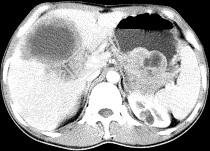

单项选择题女,61岁, 上腹部疼痛一个月,食欲减退, 消瘦,CT所见如图, 最可能的诊断是 ( )

A、肝脓肿

B、肝转移瘤

C、胃癌肝转移

D、肝包虫病

E、原发性肝癌